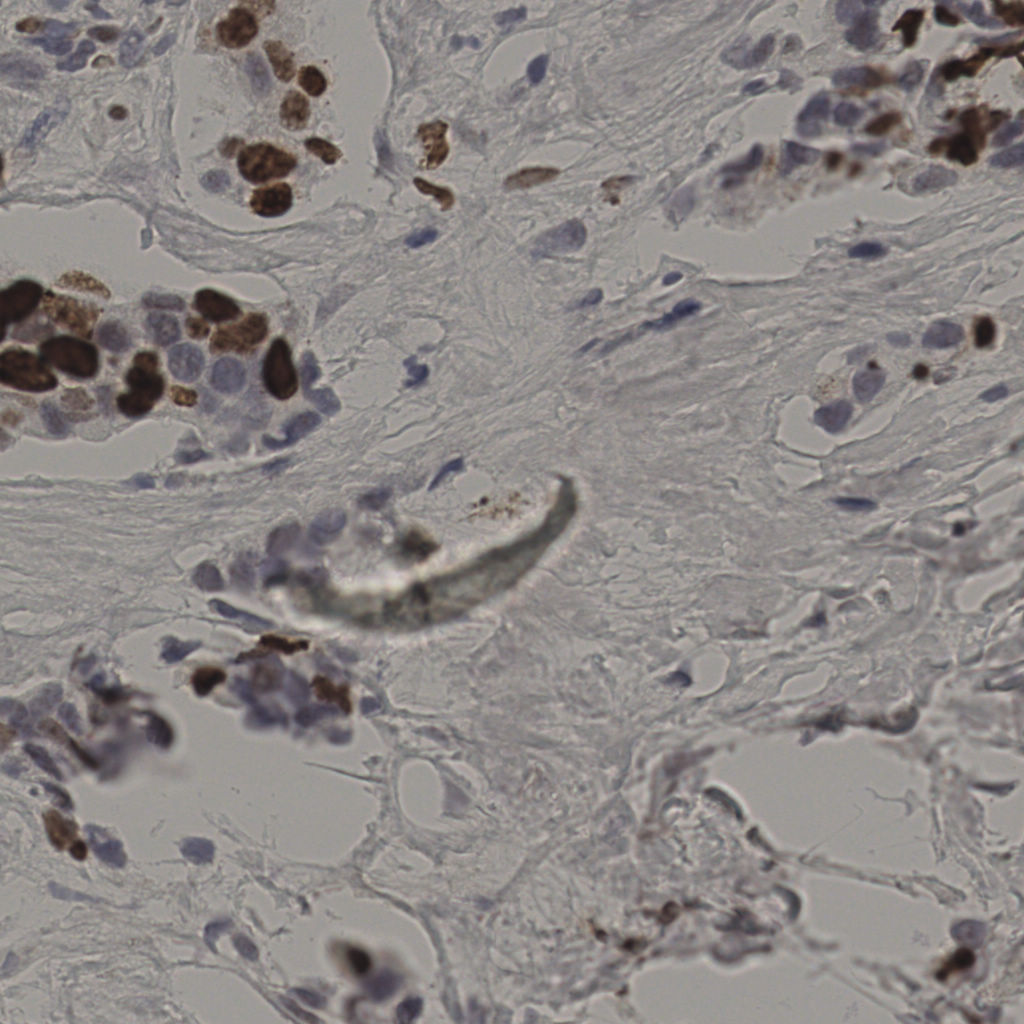

17.75%

Ki67 指数

阴 7986

阳 1723